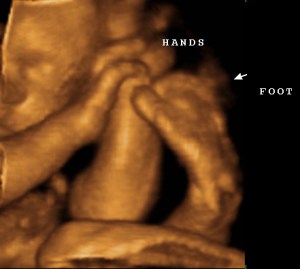

NOSE! Just look at that little pinchable nose! Here we are, at 29 weeks, and believe it or not, there appears to be a REAL baby in my belly! WHOA! talk about sci-fi crazy talk! She’s got a full head of hair, no you can’t see it….that black stuff that might look like hair, is actually her favorite pillow…my bladder. But she has, little hands and feet, pouty lips and appears to be a super cuddler! YAY!